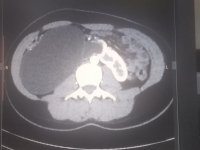

У Львові прооперували жінку, в якої була пухлина з 9 л рідини всередині

28-річну жінку у Львові прооперували, аби забрати кістому яєчника розміром з відро – вона не розуміла, чому в неї росте живіт.